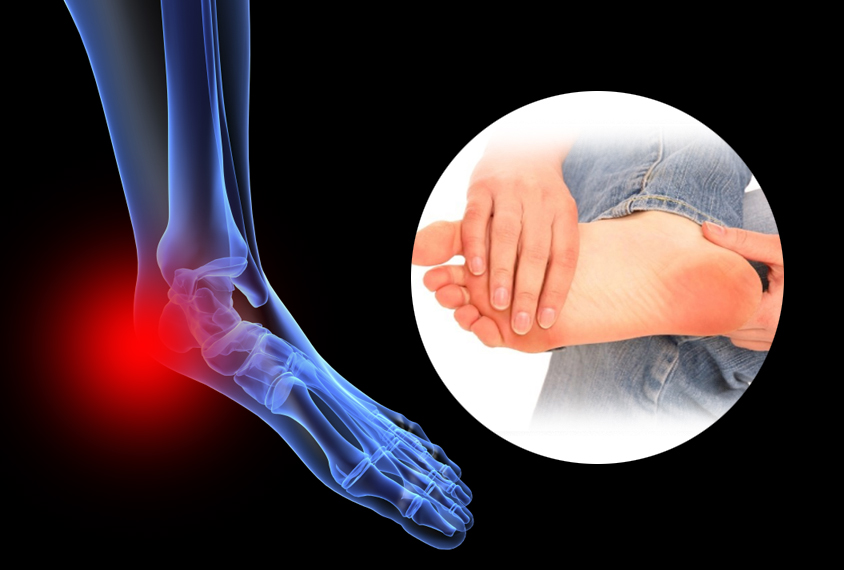

초기에는 밤에만 불편함을 느끼다가 점점 지속 시간도 늘어납니다.3. 족저근막염

발바닥 통증의 대표 질환으로,

발뒤꿈치에서 발바닥 전체로 이어지는 근막에 염증이 생기며

걷거나 서 있을 때 발바닥이 뜨겁고 찌릿한 통증을 유발합니다.

특히 아침에 첫 발을 디딜 때 더 아픈 경우가 많아요.